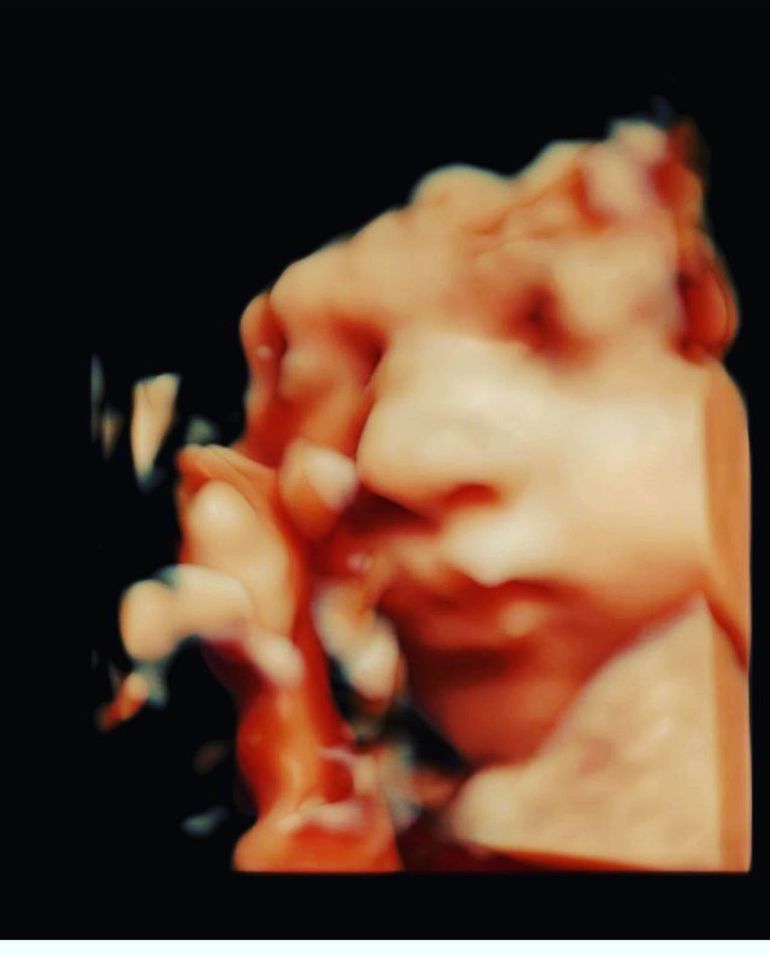

Laurențiu Reghecampf a postat prima imagine cu chipul celui de-al treilea fiu al său! Ce nume a ales pentru băiețel?